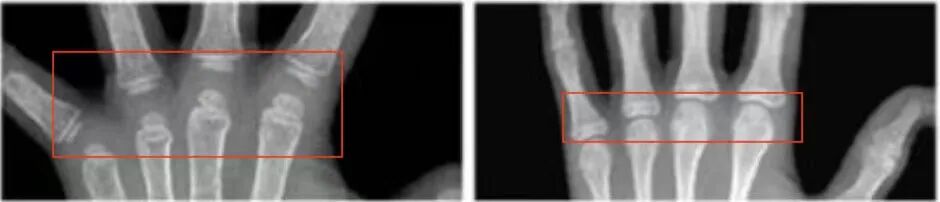

預(yù)測(cè)骨齡,專(zhuān)家建議選擇單腕關(guān)節(jié)正位片,由相關(guān)經(jīng)驗(yàn)的醫(yī)生來(lái)作出判斷。一般依據(jù)左手的X線結(jié)果:

1.依據(jù)骨間距。間距越大,生長(zhǎng)的空間越大,骨齡越小。

(骨齡小時(shí),骨間距相對(duì)較大)

2.依據(jù)腕骨的多少、密度來(lái)判斷。腕骨越少,生長(zhǎng)空間越大,骨齡越小。

(骨齡越小,腕骨數(shù)量、密度越?。?/span>